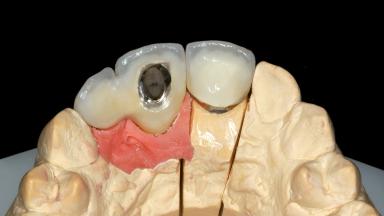

Replacement of an Upper Right Central and Lateral Incisor with an Implant-Supported Crown and a Distal Cantilever

Abutment Type Customized

Prosthesis Type FDP